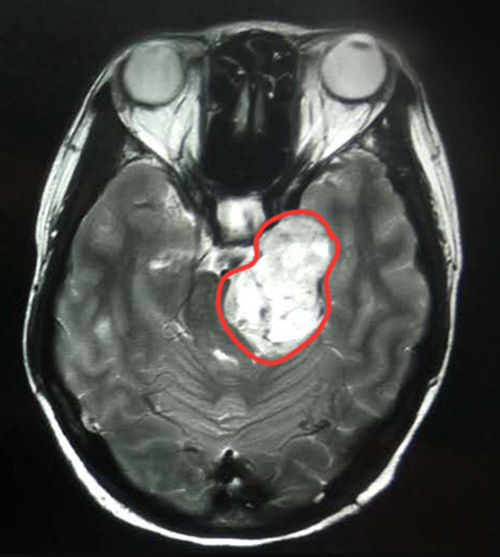

陈女士的MRI影像诊断报告单很快出来了,结果让她大吃一惊。MRI影像显示,患者左侧桥小脑角区见团块状异常信号病灶,边界清晰,大小约4.8*3.3厘米,肿瘤呈哑铃状生长,左侧三叉神经显示不清,临近脑干受压,第四脑室受压变形,是一枚体积不小的三叉神经鞘瘤。

▲MRI影像显示,左侧桥小脑角区有一4.8*3.3厘米的肿瘤